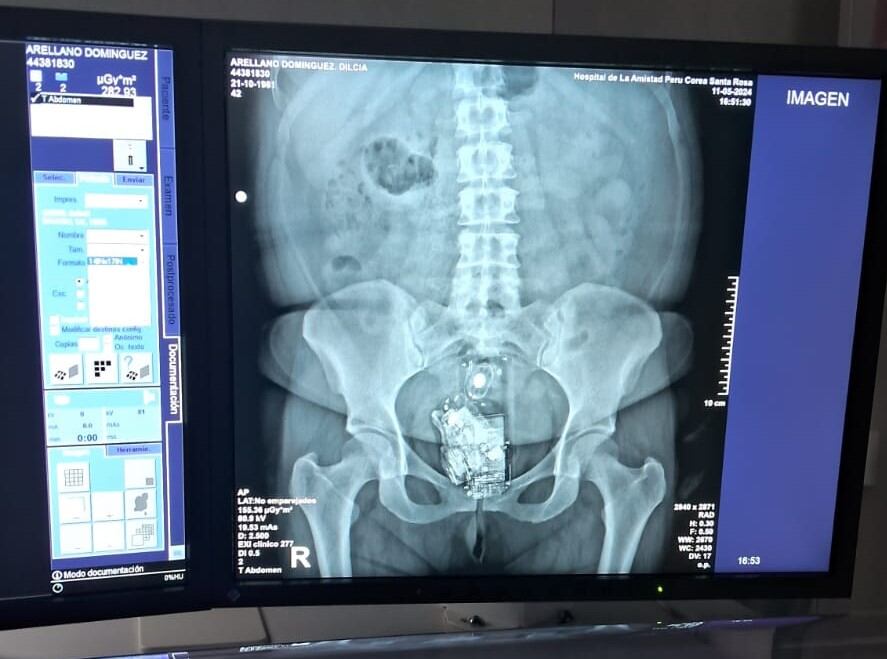

Durante la revisión corporal a Romsery Arellano Domínguez Dilcia, se activó la alerta de presencia de cuerpo metálico a la altura de las partes íntimas. Tras realizarle una ecografía, se encontró que tenía dos celulares y un cargador.